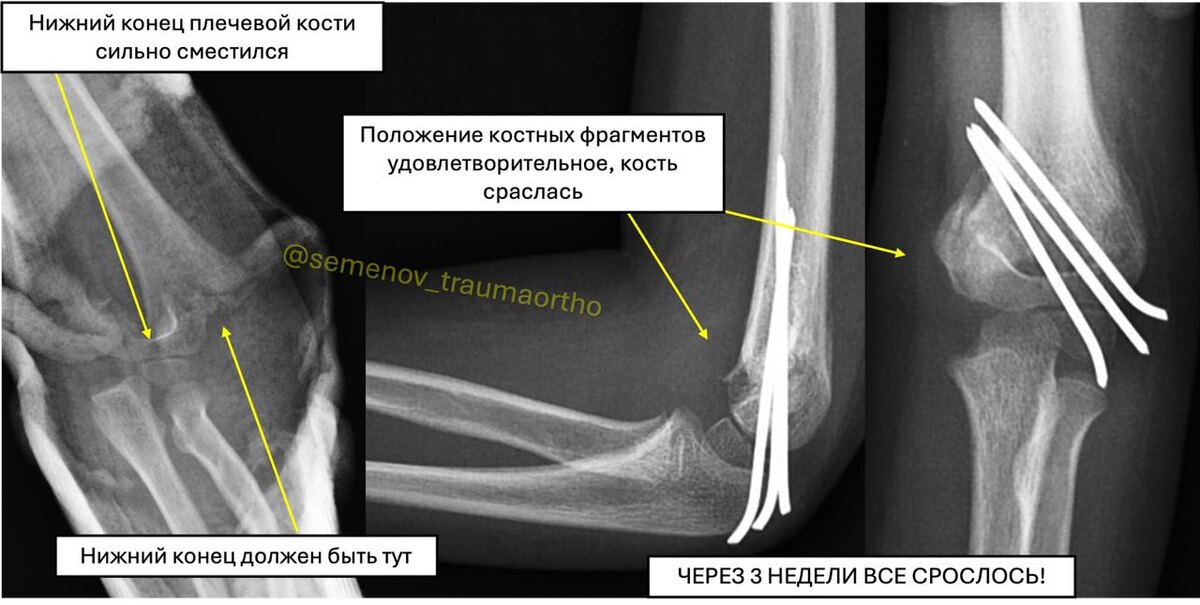

➡️🤸‍♀️ Падение с качелей = сложный чрезмыщелковый перелом 🛠️ 👋Привет, друзья! С вами Андрей Семенов. 👨‍⚕️ 👇Сегодня расскажу о непростом, но очень показательном случае из практики – лечении сложного перелома плечевой кости у маленькой пациентки. 🔜Наша героиня – девочка 4 года 7 месяцев. 💀В один из майских теплых дней (представляете, были теплые дни😃) девочка упала с качелей на улице на вытянутую левую руку. 🚨 Результат: резкая боль, выраженный отек локтевого сустава. 🚑 Родители молодцы – сразу обратились в травмпункт, где сделали рентген и наложили гипсовую лонгету. 🟡Оттуда бригада СМП доставила маленькую пациентку к нам, в ДГКБ им. Н.Ф. Филатова. ✔️Диагноз – Закрытый чрезмыщелковый перелом левой плечевой кости со смещением. 🆘Это один из самых "коварных" переломов у детей в области локтевого сустава и один из самых сложных переломов для закрытой репозиции! 💀По классификации Gartland, такие переломы со значительным смещением относятся к III типу (как на фото выше). ?

✔️Диагноз – Закрытый чрезмыщелковый перелом левой плечевой кости со смещением.

💀По классификации Gartland, такие переломы со значительным смещением относятся к III типу (как на фото выше).

📎Особенность Gartland III типа: Это крайне нестабильный перелом, где отломки полностью смещены и не контактируют друг с другом.

При этом они смещаются не только в стороны, но и с разворотом (ротацией).

• Под общей анестезией (наркозом), под контролем рентген-аппарата (ЭОП), мне удалось закрыто (то есть без разрезов!) сопоставить отломки – это называется репозиция.

• Затем, для надежной фиксации, через небольшие проколы кожи были проведены три металлические спицы диаметром 1,8 мм.

✅ Контрольные снимки в операционной показали: отломки стоят идеально, ось кости восстановлена, фиксация стабильная!

🟡Через 3 недели перелом сросся!